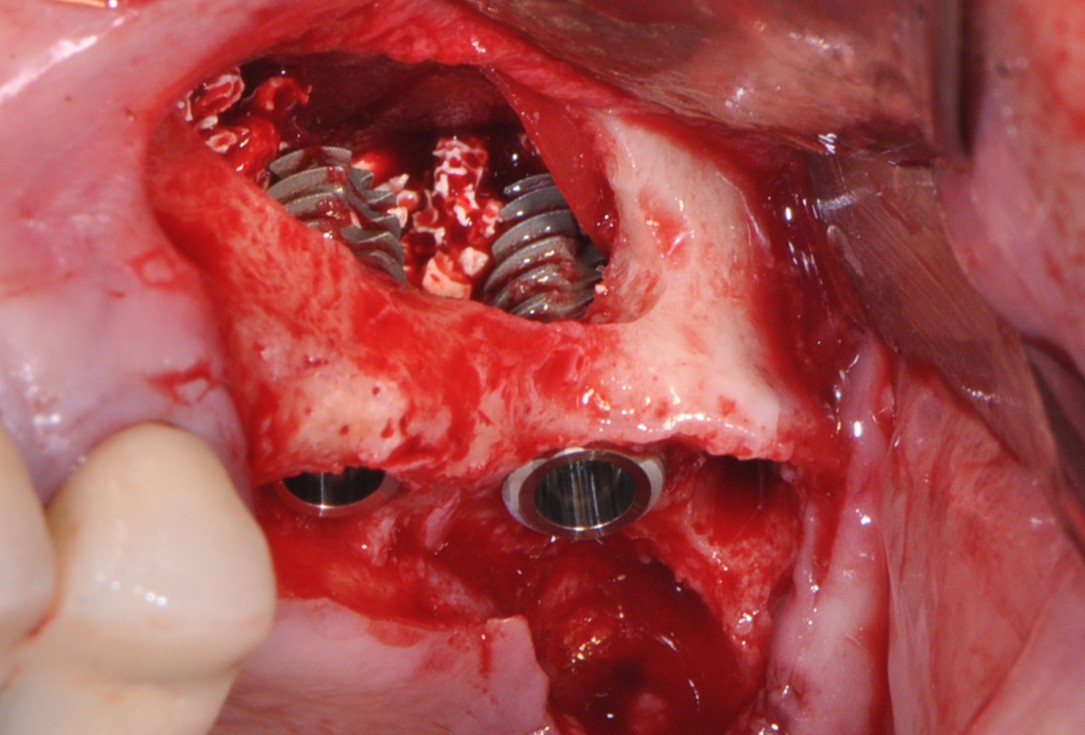

7/16 - Dental implants placement

One-stage sinus lift - Dr. V. Kalenchuk

8/16 - Filling subantral cavity with cerabone® 1.0 -2.0 mm particle size

One-stage sinus lift - Dr. V. Kalenchuk